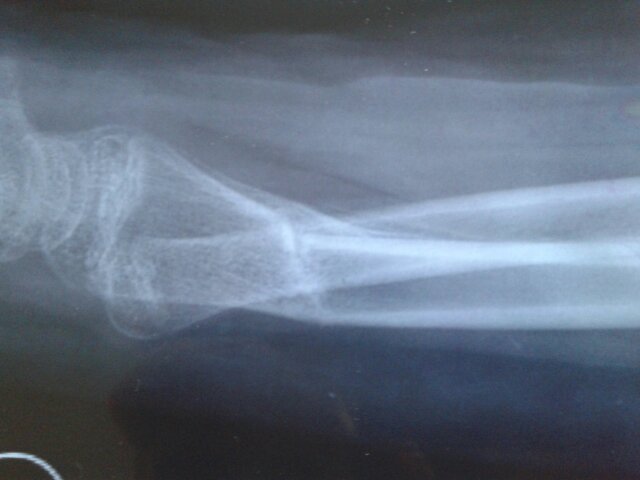

左桡骨远端骨折2月的片子,现15岁男孩左胳膊向背拱,而且关节向上时有东西卡住似的,该如何? 点击展开 匿名用户 2016-03-10 09:00 满意回答 看片子骨折对菠涉位和战狼愈合情况还是不错,现在关节活动有问题,是因为骨折治疗期间活动少引起,需要进行功能锻炼。梨指慕 ²¿L 2016-03-10 09:02 宝宝知道提示您:回答为网友贡献,仅供参考。 相关问题 15岁男孩,左桡骨远端骨折,两月拍片有成角,现在胳膊向背拱,而且腕关节向上有卡住似的,怎么锻炼能使 肘关节疼痛已有4个多月,一伸直胳膊使劲攥拳… 三周前,肘关节后侧脱位,复位后打石膏,现在胳膊无法…